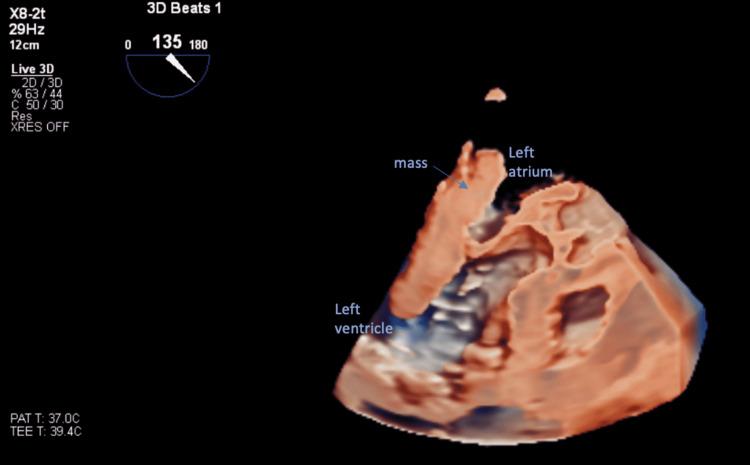

A 75-year-old Caucasian female with a past medical history including insulin-dependent diabetes mellitus, hypertension, and dyslipidemia, presented to the emergency room for having palpitations for three weeks. Echocardiography revealed a very large left atrial mass mimicking myxoma. Mass was excised and examined by pathology, revealing a mural thrombus. A mural thrombus is not an uncommon mass found in the left atrium. However, it does not often present symptomatically, strongly mimics an atrial myxoma on cardiac imaging, and has rarely ever been reported to be greater than seven centimeters in any dimension. We present a case of a 75-year-old Caucasian woman with a massive, symptomatic cardiac thrombus masquerading as a myxoma on imaging.

一名75岁的白种女性,既往有胰岛素依赖型糖尿病、高血压和血脂异常病史,因心悸三周就诊于急诊室。超声心动图显示左心房有一个非常大的肿块,类似黏液瘤。肿块被切除并送病理检查,结果显示为壁血栓。壁血栓在左心房并不罕见。然而,它通常没有症状,在心脏成像上与心房黏液瘤极为相似,而且从未有过任何维度大于7厘米的报道。我们报告一例75岁白种女性病例,其心脏有一个巨大的、有症状的血栓,在影像学上伪装成黏液瘤。